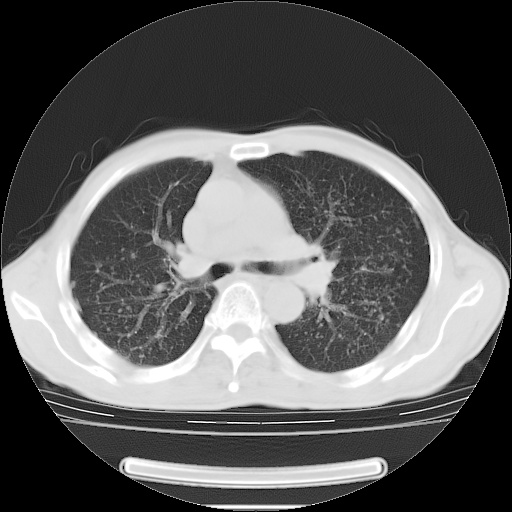

标题: CT15131:M63Y,胸痛2月,加重一周 [打印本页]

男性患者,63岁。右侧胸背部疼痛2月,加重一周。

考虑:右肺中央型肺癌并右肺下叶不张;两肺尖继发性肺结核。

还有纵隔多处肿大淋巴结及肋骨的改变、两肺多发结节灶。

右肺下叶支气管狭窄闭塞,右下肺不张,气管前间隙淋巴结肿大,两上肺散在分部粟粒灶,沿肺血管支气管束分部,血管支气管束走形较为光滑。考虑右肺中心型肺癌合并肺不张,纵隔淋巴结转移,两上肺癌性淋巴管炎

右肺下叶中心性肺癌并纵隔淋巴结转移,左侧肋骨转移。双肺上叶继发性结核表现。

1)右肺下叶中心性肺癌并纵隔淋巴结转移,两肺转移,左侧肋骨转移。2)双肺上叶继发性结核。

右肺下叶中心性肺癌并纵隔淋巴结及两肺、左侧肋骨转移。双肺上叶继发性结核表现。